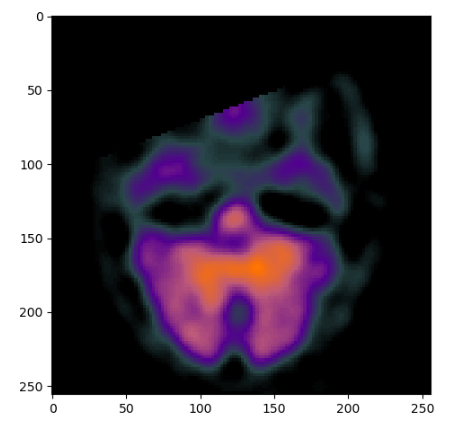

import matplotlib.pyplot as plt

plt.imshow(spect)

plt.show()